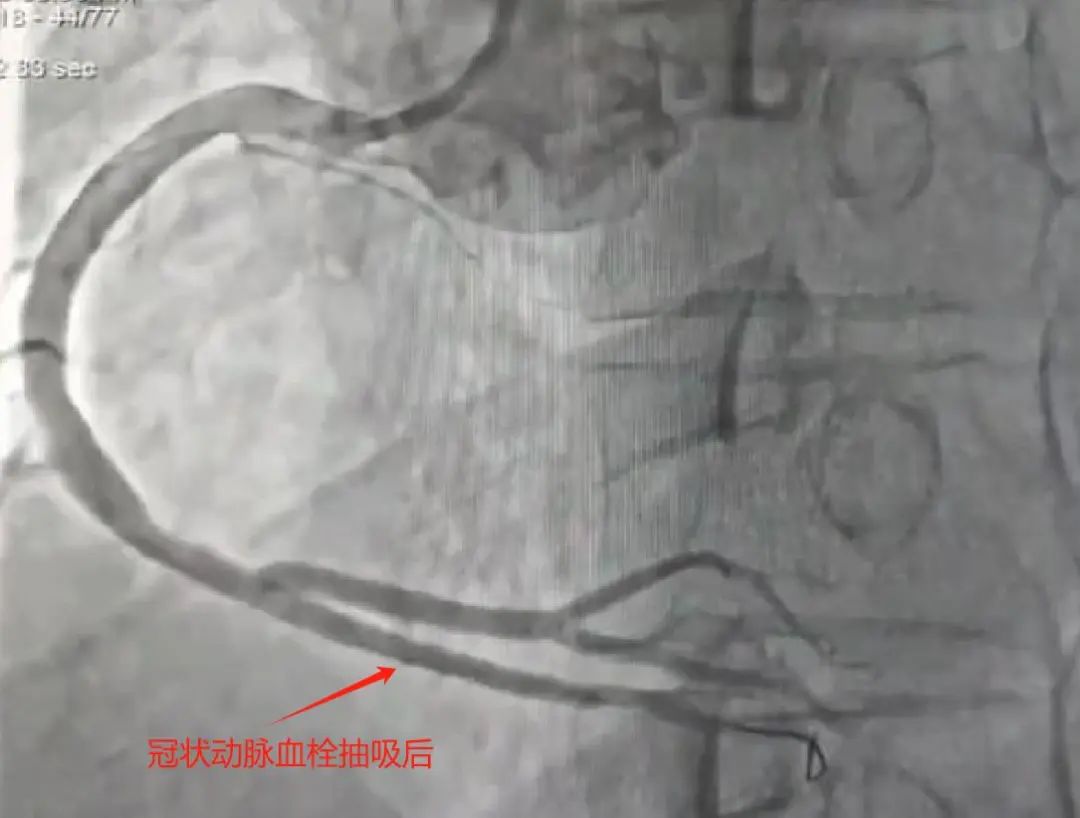

术中所见:右冠状动脉粗大,远段狭窄60-70%,后降支开口近段毛玻璃状大血栓,果断为患者实施了血栓抽吸术,抽出新鲜红色血栓,考虑患者年纪轻,右冠状动脉远段病变临界,本着无植入原则,使用药物球囊充分扩张病变,复查造影无残留血栓,治疗效果满意。